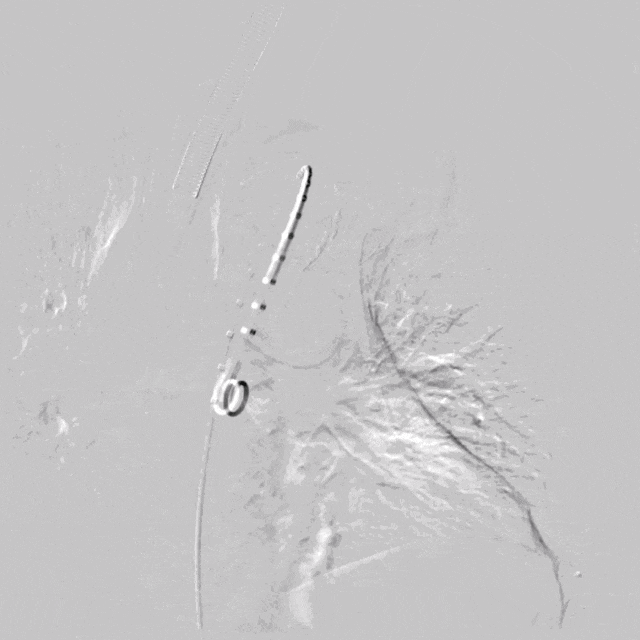

使用3mm*30mm球囊扩张窗口,改变DSA角度证实破膜成功

泥鳅导丝怎么用符伟国/王利新教授团队:0.035"普通泥鳅导丝进行胸主动脉弓上分支原位开窗的病例分享_https://www.jmylbn.com_新闻资讯_第18张

进一步使用6mm*40mm球囊扩张开窗口